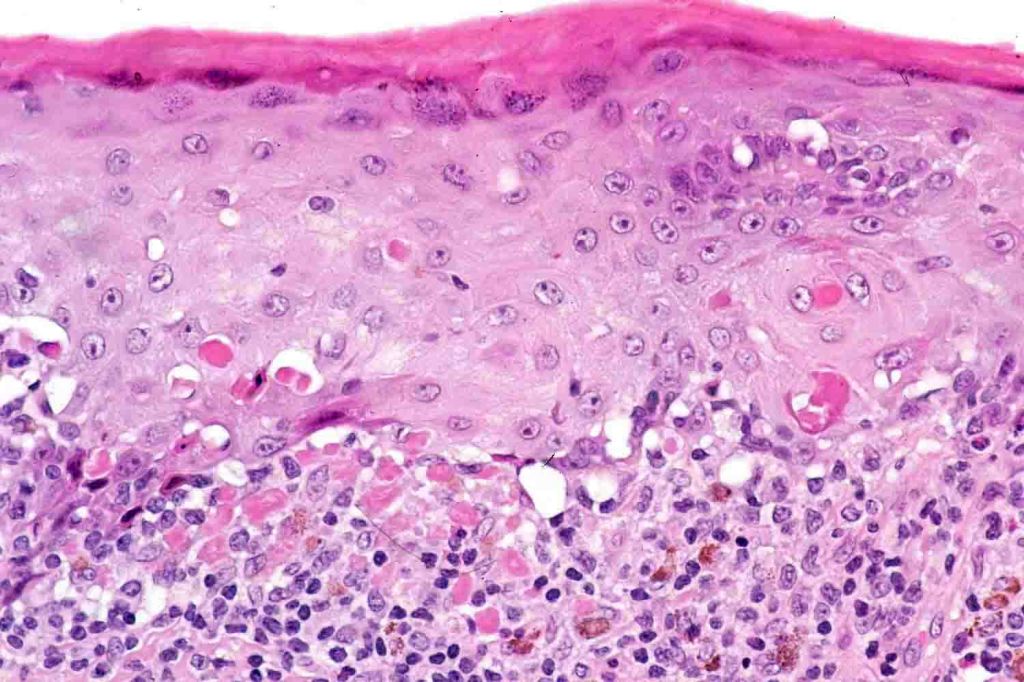

•Hyperkeratosis +/- parakeratosis

•Wedge-shaped hypergranulosis

•Generally irregular (sometimes saw-tooth) acanthosis but may show broad acanthosis

•Interface change

•Conspicuous cytoid bodies

•Pigment incontinence

•Band-like or perivascular infiltrate of lymphocytes, histiocytes with occasional eosinophils & plasma cells